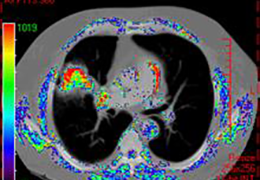

ANYTHINK 经导管主动脉瓣膜置换术分析系统